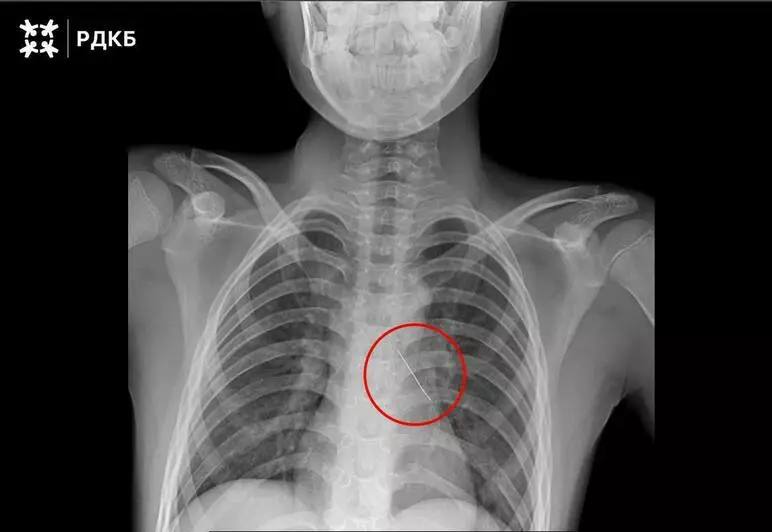

В Москве хирурги спасли ребёнка из Калининграда который вдохнул булавку Изогнутая французская булавка пронзила бронх что могло привести к серьезным нарушениям дыхания и даже коллапсу легкого 11 летнего пациента доставили в столицу бортом санавиации Мальчик мог только шептать и испытывал сильные боли Хирурги извлекли инородное тело с помощью оптических щипцов Кровотечение купировалось самостоятельно Через три дня после успешной операции ребёнка выписали Фото тг канал Российской детской клинической больницы